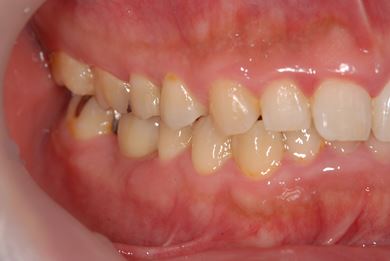

インプラントの症例写真 IMPLANT

抜歯即日スピードインプラント治療

| 性別/年齢 | 男性 / 38歳 | ||||||||||||||||||||||||||||||||

| 主訴 | 10年位前に虫歯治療をした右下奥歯のつめ物が取れ、再治療を受けた際にインプラントをすすめられたため、治療相談で来院。 | ||||||||||||||||||||||||||||||||

| 治療方針 | 抜歯と同時にインプラントを埋入し、治療期間を短縮する。 | ||||||||||||||||||||||||||||||||

| 治療内容 | インプラント1本(抜歯即日スピードインプラント)、ハイブリッドセラミッククラウン1本 | ||||||||||||||||||||||||||||||||

| 総治療費 | 257,250円 | ||||||||||||||||||||||||||||||||

| 治療期間 | 6ヶ月 |